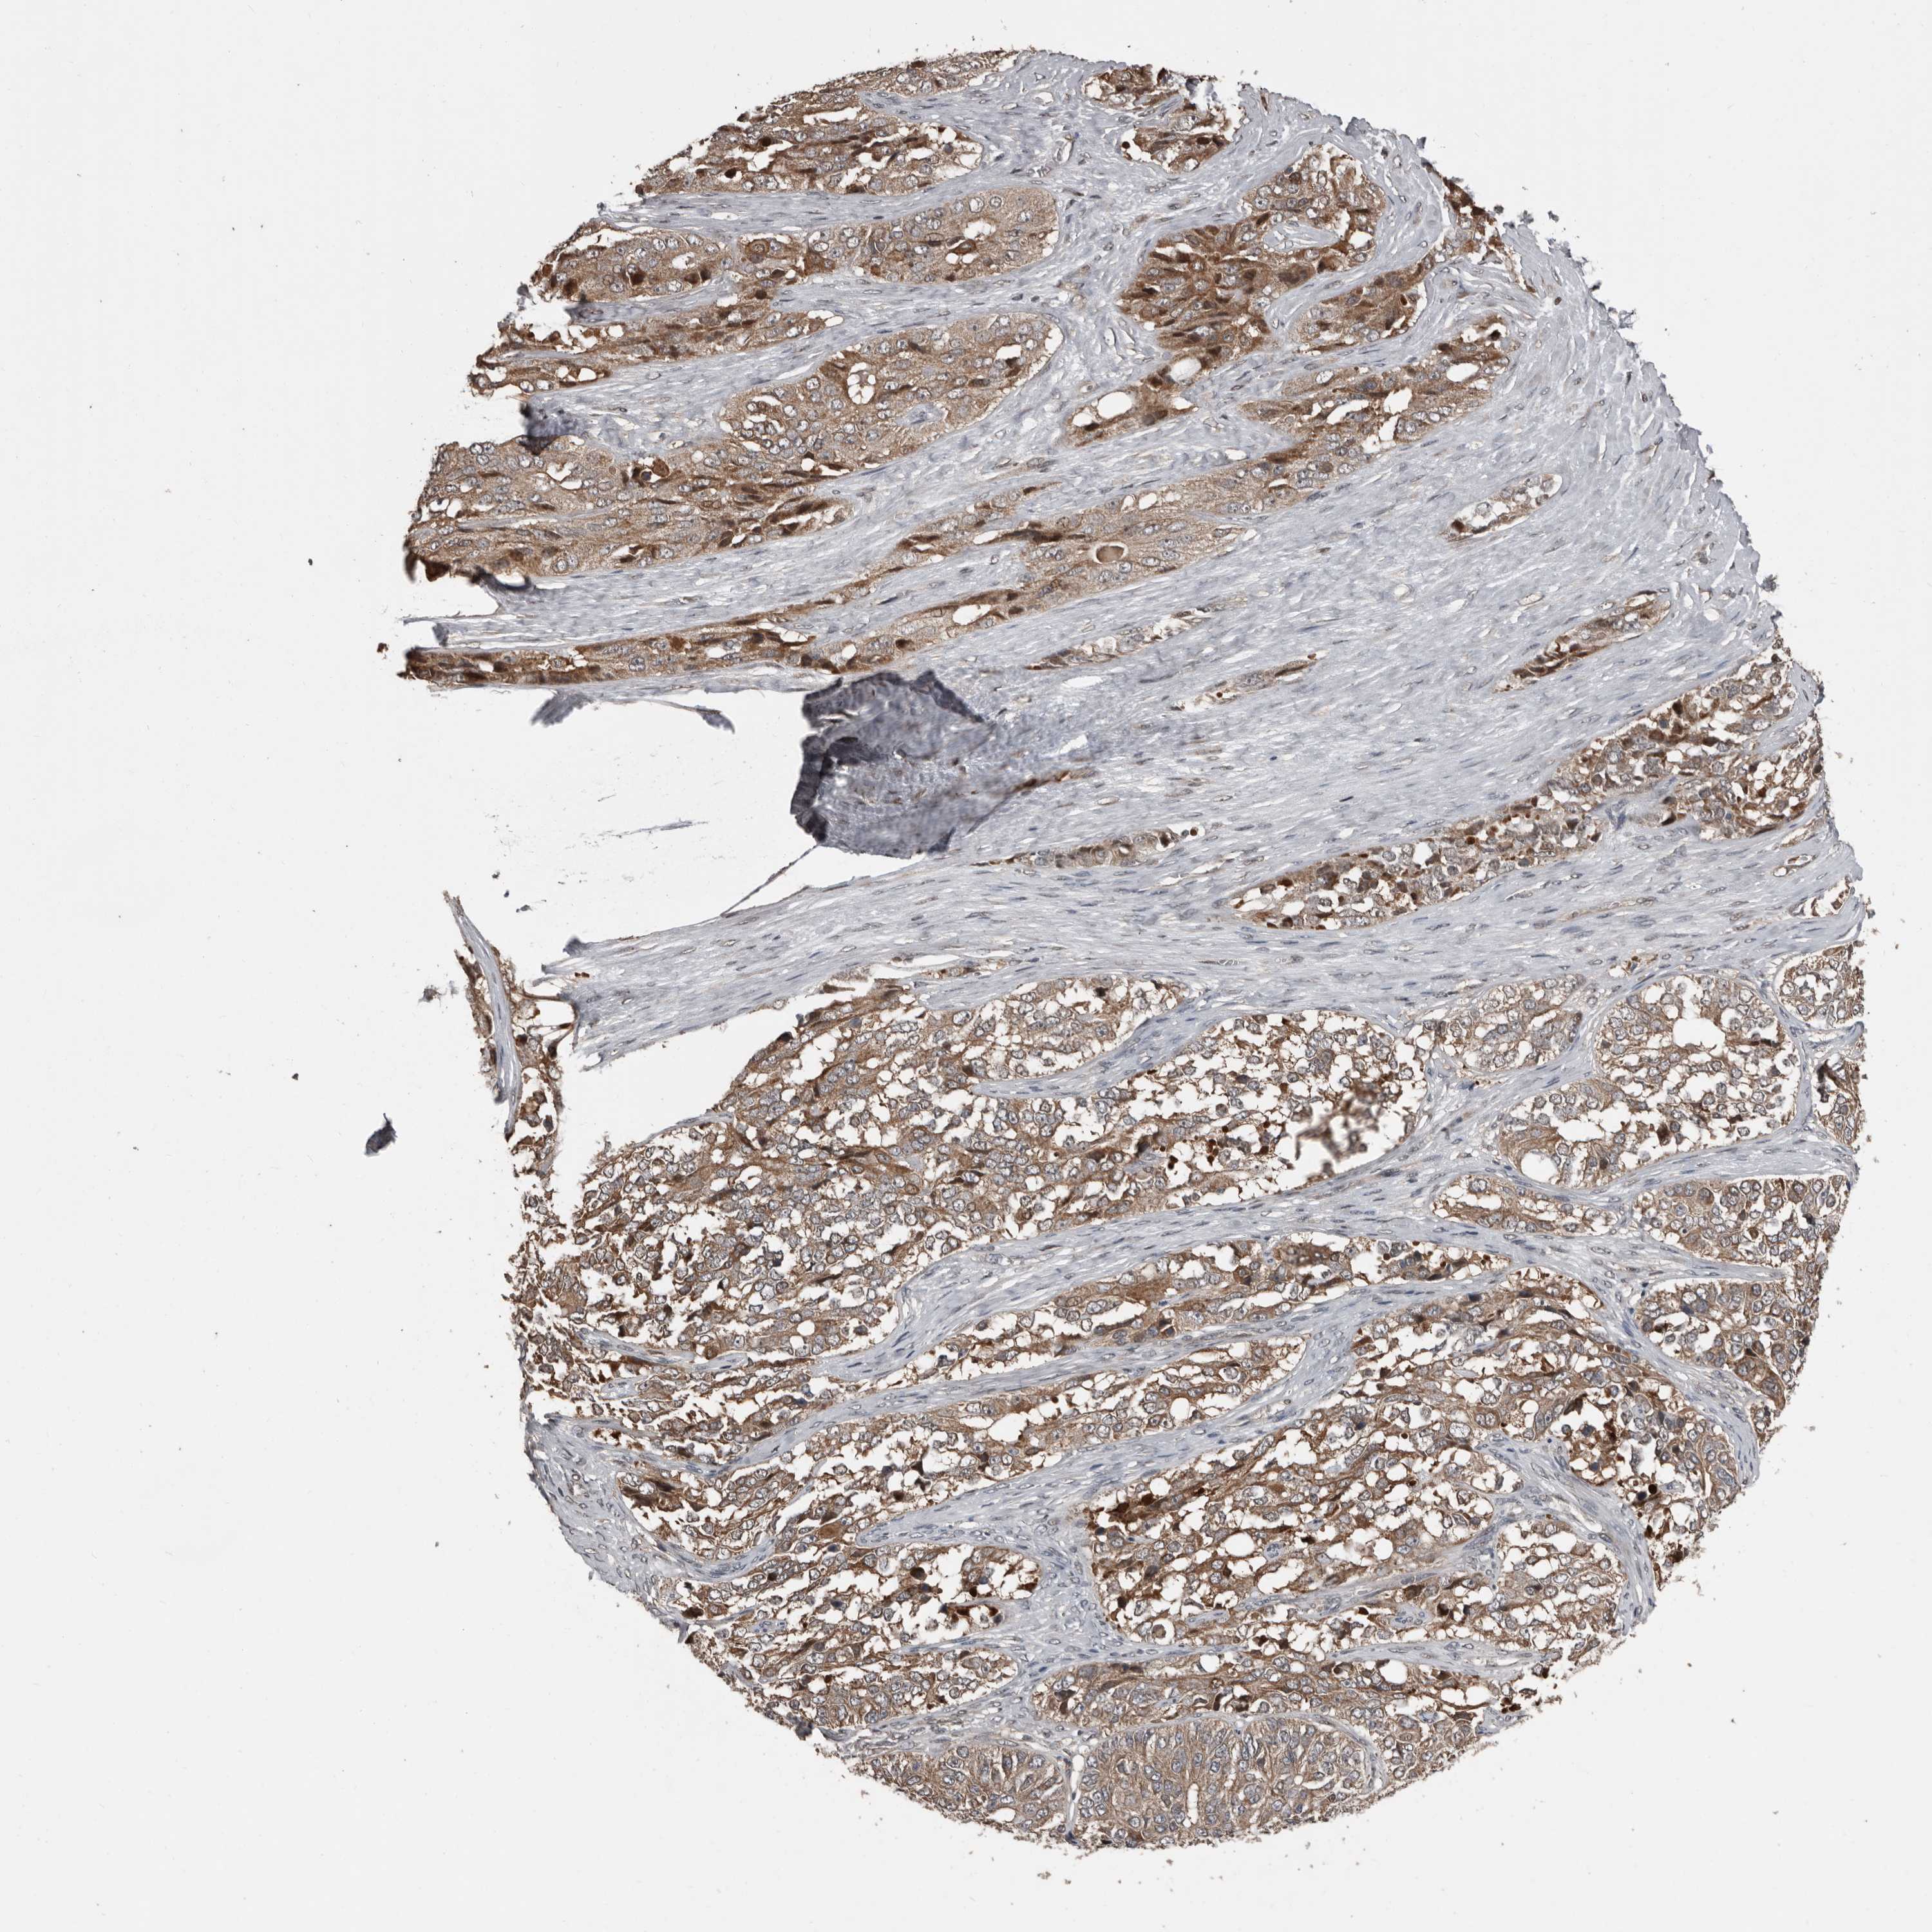

OVARIAN CANCER - Protein expressioni

A mouse-over function shows sample information and annotation data. Click on an image to view it in a full screen mode. Samples can be filtered based on level of antibody staining by selecting one or several of the following categories: high, medium, low and not detected. The assay and annotation is described here.

Note that samples used for immunohistochemistry by the Human Protein Atlas do not correspond to samples in the TCGA dataset.

Antibody stainingi

Antibody staining in the annotated cell types in the current human tissue is reported as not detected, low, medium, or high, based on conventional immunohistochemistry profiling in selected tissues. This score is based on the combination of the staining intensity and fraction of stained cells.

Each image is clickable and will lead to virtual microscopy that enables deeper exploration of all samples and also displays staining intensity scores, fraction scores and subcellular localization as well as patient and tissue information for each sample.

Antibody HPA026509

Cystadenocarcinoma, serous, NOS

Carcinoma, endometroid

Cystadenocarcinoma, mucinous, NOS

Carcinoma, NOS